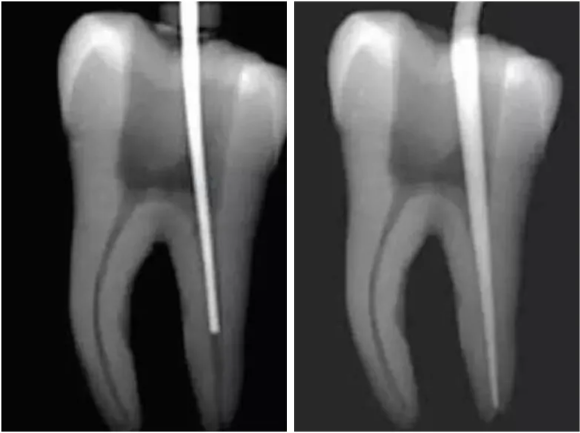

而最新的牙齿根管治疗技术:热牙胶充填,是目前临床上应用最为广泛的充填技术,其中热牙胶垂直加压充填技术的多步加热和加压改良为加热加压同时完成,让牙齿的功能恢复的更好更完美。

1.根管治疗并非都是一次完成的治疗,通常要经过开髓引流、牙髓失活、牙髓摘除、根管预备等多个步骤分3-5次完成,具体步骤则需要医生根据患者临床检查确定。